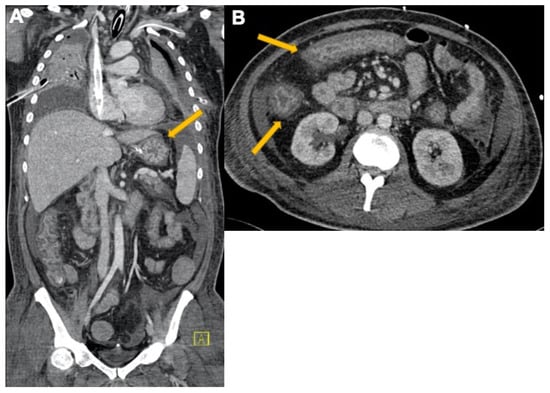

2.3. Pulmonary Embolism

3.3. Abdominal Manifestations